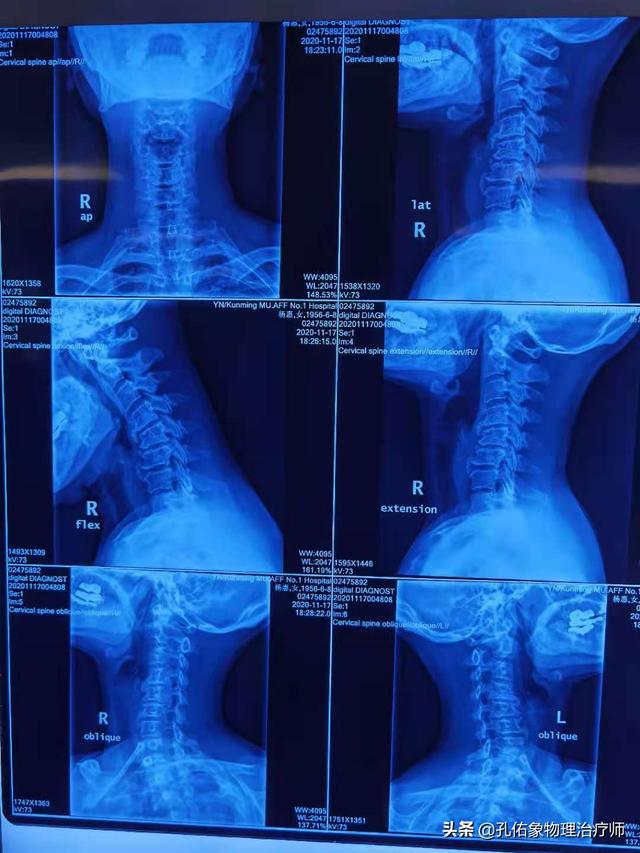

1.早期発症:ある。急性の痛みの場合、頸部のX線検査を勧めることがある。痛みを伴う関節の可動性を改善するために、頸椎の管理を目標としている。

五十肩の問題は、診断と治療のプロセスにおいて、頚椎をより考慮する必要があります。 頚椎の問題と神経の挟み込みによって痛みが引き起こされる場合、自然治癒は不可能と考えられています。